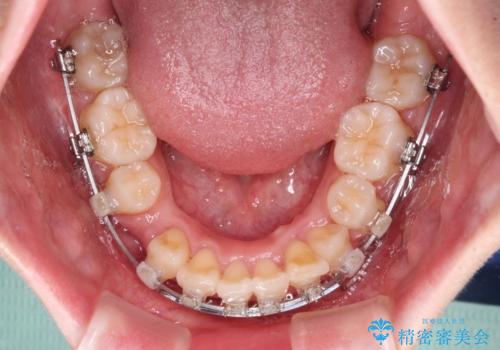

- クリアブラケット

- 3年9ヶ月

- 30回以上